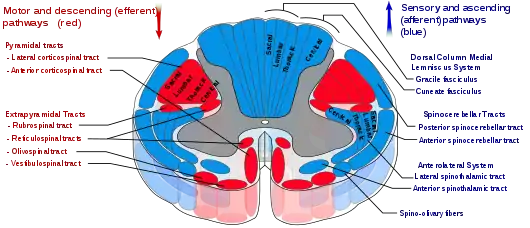

The spinothalamic tract is a sensory pathway originating in the spinal cord. It transmits information to the thalamus about pain, temperature, itch and crude touch. There are two main parts: the lateral spinothalamic tract, which transmits pain and temperature, and the anterior (or ventral) spinothalamic tract, which transmits crude touch and pressure.